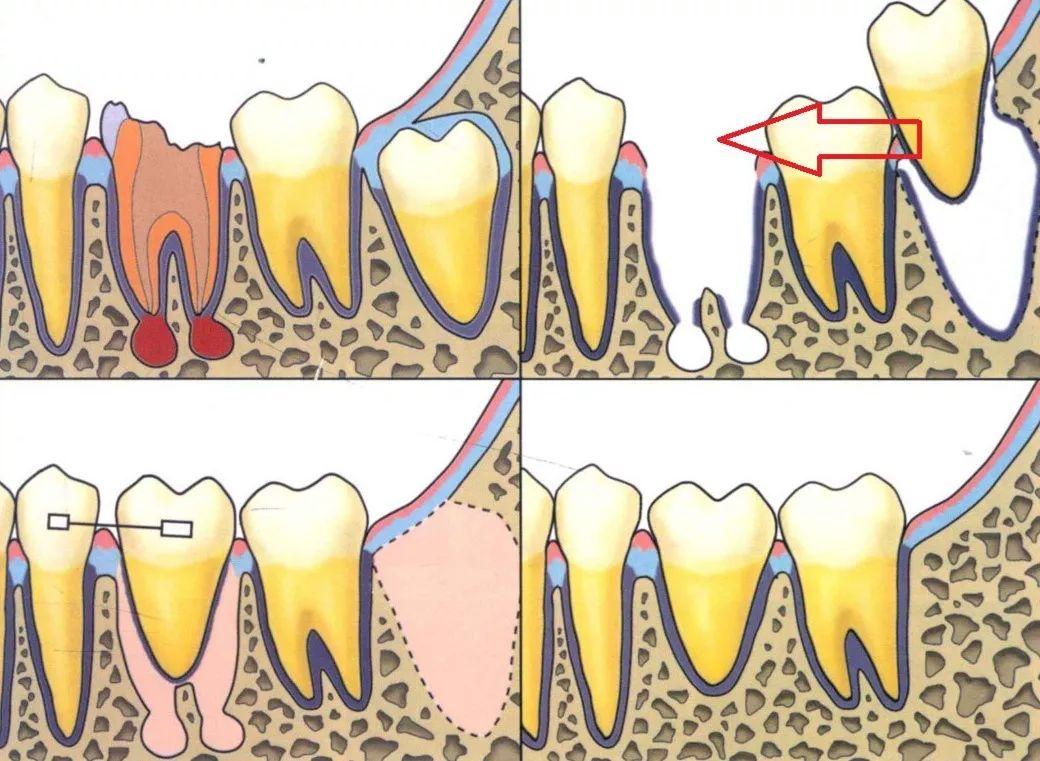

自體牙移植是指:將患者自身的埋伏牙、阻生智齒、錯(cuò)位牙或多生牙由一個(gè)位置移植到另一個(gè)位置,以代替壞牙行使功能。

利用沒有功能的阻生智齒來代替不能保留的患牙:把阻生的智齒和嚴(yán)重齲壞不能保留的患牙同時(shí)拔除,再將完好的智齒移植到患牙的牙槽窩內(nèi),通過機(jī)體自身愈合機(jī)制,智齒與牙槽骨能良好的結(jié)合,進(jìn)而替代被拔除的患牙,行使功能,即大限度的保留了天然牙,又避免了種植牙,給患者多一種的選擇。

(自體牙移植示意圖)